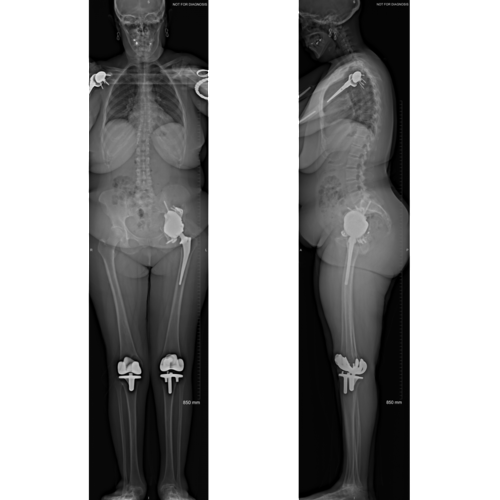

Pre-operative radiographs showing the patient’s left hip after the first stage procedure. The surgical clips are present. Note there are surgical clips in the inguinal region for the ilioinguinal approach to free the intrapelvic vessels and further clips posteriorly to access and remove the acetabular cup.

Post-operative images after the second stage of the patient’s procedure. The implant is holding together the superior and inferior aspects of the patients left hemipelvis.

Post-operative EOS images demonstrate the implant in a functional position. There is no functional leg length discrepancy or pelvic tilt.